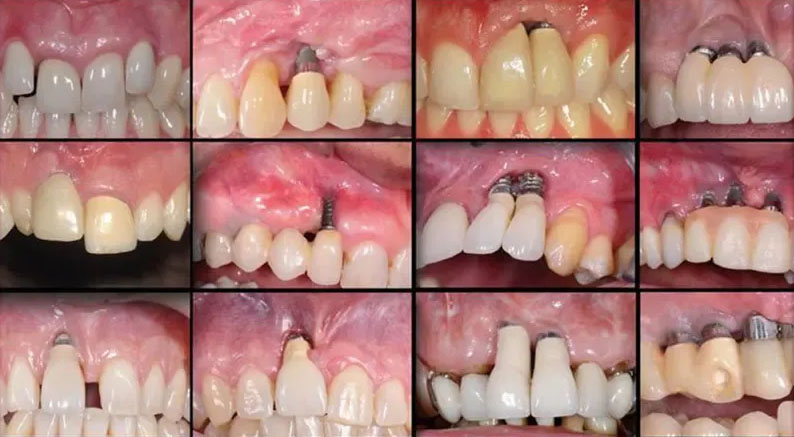

Dental Implant Smile Makeover Results

Dental implants provide a permanent solution for missing teeth, delivering both aesthetic and functional benefits.

Procedure Highlights:

Titanium implants placed into jawbone

Healing and integration phase

Placement of crowns or bridges

Results:

Natural-looking teeth

Improved confidence and speech

Long-lasting durability

Price Comparison (per implant):

USA: $3,000 – $6,000

Philippines: $800 – $1,500

Failed Dental Work Correction Case

Some patients arrive with failed crowns, bridges, or implants due to poor workmanship or infection.

Common Issues:

Loose or broken crowns

Gum infection around implants

Misaligned bite

Corrective Treatment:

Removal of failed restorations

Infection control and bone support

Replacement with high-quality prosthetics

Outcome:

Restored function and comfort

Improved aesthetics

Prevention of further complications